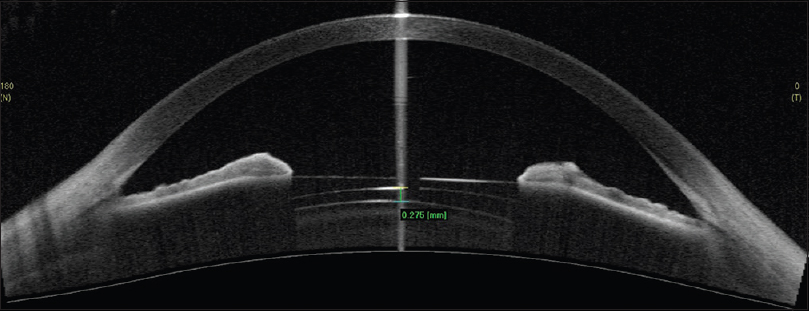

El implante de la lente ICL se realiza en la cámara posterior posterior del ojo, detrás del iris y delante del cristalino y existen diferentes tamaños de diámetro para adaptarse a los diferentes tamaños de anatomía intraocular (12.1, 12.6, 13.2, y 13.7 mm). La distancia postoperatoria entre la lente ICL y la cápsula anterior del cristalino y al que se le denomina Vault, es el determinante postoperatorio más importante que existe como medidor de la seguridad del implante de la lente.

Es por tanto clave la selección del diámetro de la lente a implantar puesto que dependiendo del tamaño de la lente ICL implantada tendremos el Vault resultante para cada caso. Así se ha reconocido una distancia de seguridad de Vault dentro de los cuales no se presentan efectos adversos ni a corto ni a largo plazo y de la misma manera un Vault fuera del rango de seguridad puede presentar riesgo de eventos adversos específicos, incluyendo el bloqueo pupilar, catarata subcapsular anterior, dispersión de pigmentos y glaucoma. De este modo, los extremos de los rangos de Vault de seguridad deben ser considerados como factores de riesgo de eventos adversos y no como eventos adversos en sí mismos.

– Gonvers et al concluyeron en su estudio que aunque un Vault ≤90 micras fue un factor de riesgo para el desarrollo de cataratas subcapsulares anteriores, en su estudio la mayoría de los ojos con Vault en ese rango mantenían cristalinos sin opacificación. Evidenciaron igualmente que los niveles más altos de miopía constituían un factor de riesgo de cataratas subcapsulares anteriores en aquellos Vaults ≤90 micras y concluyeron que 150 micras debía ser considerado como un límite inferior de Vault de seguridad puesto que era en esa distancia cuando no había contacto (hasta la periferia media de la ICL) entre la ICL y el cristalino independientemente del modelo de ICL y del grado de miopía. Esto es así pues en los modelos de mayor corrección de la miopía el diseño de la lente ICL es de mayor grosor en la periferia.

– Schmidinger et al observaron un adelgazamiento gradual del Vault con el tiempo de aproximadamente 20 micras por año, por lo que veían procedente un Vault central mínimo de 230 micras.

– Maeng et al definieron como un Vault mínimo de seguridad el de 250 micras o más y a tenor de los resultados de su estudio consideraron factores de riesgo de obtención de Vault mínimos a los pacientes mayores de 45 años, pues el volumen del cristalino es mayor en esa edad y a los pacientes con equivalente esférico > 14 dioptrías, pues el grosor de la lente es mayor en esos casos en la periferia.

-Alfonso et al concluyeron que con un Vault central de 260 micras se conseguía evitar el contacto en la periferia de la lente ICL y el cristalino incluso en altos grados de miopía.

– Así según los diferentes autores deben de estimarse unos rangos de seguridad del Vault de entre 260 a 1.000 micras, siempre que la estructura de ángulo de la cámara anterior y su función permanezcan normales. Así el insuficiente o excesivo Vault debe considerarse como un factor de riesgo, no una complicación y sólo un porcentaje de ojos con Vault más allá del rango predefinido experimenta efectos adversos si bien deben ser exhaustivamente seguidos y valorados.